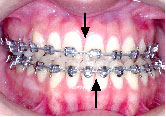

上あごは左へ2mm,前方へ2mm(Le Fort 1型)、下あごは右後方へ3.5mm,正面右へ3mm、左後方へ2.5mm(IVRO)、また顔のバランスをとるためあごの先を前方に5mm移動しました。(genioplasty)手術が終わり、退院当日にできるだけ来院していただきます。この方は手術後13日目でした。

手術前に製作して渡しておいた装置(オルソサージカルスプリント)を入れ、ゴムをかけた状態できていただきます。

術前矯正がうまくいったので術後矯正は微調整で済みました。